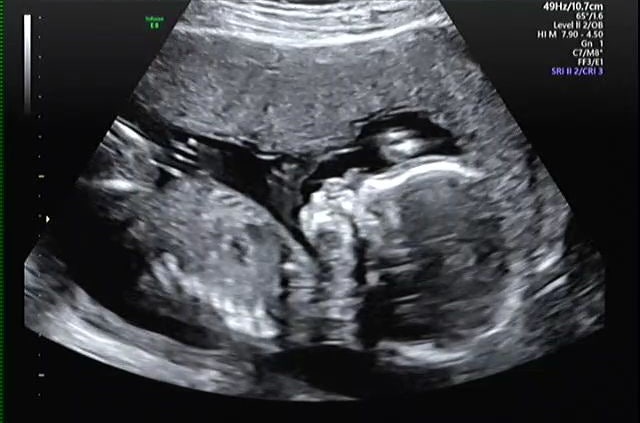

17 주간의 성별 공개

17 주의 가장 큰 문제는 우리의 성별이 처음 석방 된 것입니다! Doo -dao ~~~ ♡

우리의 맥동은 왕입니다. >